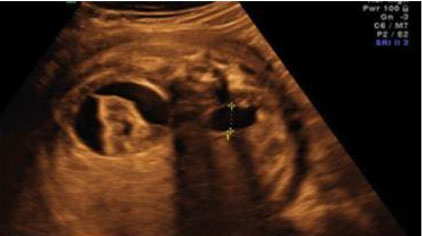

Ultrasound findings for pyelectasis are most often bilateral [19] (Figure 6). Pyelectasis is diagnosed by measuring the antero-posterior (AP) diameter of the renal in an axial plane. Longitudinal views are helpful to rule out hydronephrosis and identify a distended ureter if present.

Urinary tract dilation (UTD) A1: AP diameter 4<7 mm (<27 weeks), 7–<10 mm (>27 weeks).

UTDA2: ≥7 m (<27 weeks), ≥10 mm (≥27 weeks) or any calyceal or ureteral dilation.

Repeat ultrasound imaging in 4–8 weeks to look for progression. Postnatal ultrasound may also be helpful in establishing prognosis. Because of its association with pyelectasis, look for other soft markers of aneuploidy. To rule out reflux, consider a voiding cystourethrogram postnatally [18] (Figure 6).

Figure 6: Ultrasound image showing bilateral pyelectasis with AP diameter measurements [41]. Radiological images were obtained from open-access article distributed under the terms of the Creative Commons Attribution License (CC BY) [41].